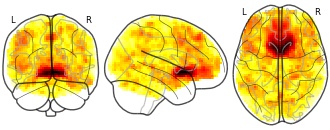

EmailClick to copy linkLink copied Cite(2021). Effects of bariatric surgery on resting state functional connectivity of the NAcc (reward network) and PCC (default mode network): Average NAcc (RN) connectivity map adjusted for age and sex [Dataset]. http://identifiers.org/neurovault.image:441789niftiAvailable download formatsUnique identifierhttps://identifiers.org/neurovault.image:441789Dataset updatedMar 22, 2021License

Cite(2021). Effects of bariatric surgery on resting state functional connectivity of the NAcc (reward network) and PCC (default mode network): Average NAcc (RN) connectivity map adjusted for age and sex [Dataset]. http://identifiers.org/neurovault.image:441789niftiAvailable download formatsUnique identifierhttps://identifiers.org/neurovault.image:441789Dataset updatedMar 22, 2021LicenseCC0 1.0 Universal Public Domain Dedicationhttps://creativecommons.org/publicdomain/zero/1.0/

License information was derived automaticallyDescriptionacross all timepoints and based on GSR-denoised data

Collection description

Obesity imposes serious health risks and involves alterations in resting-state functional connectivity of brain networks involved in eating behavior. Bariatric surgery is an effective treatment, but its effects on functional connectivity are still under debate. In this pre-registered study, we investigated the effects of bariatric surgery on major resting-state brain networks (reward and default mode network) in a longitudinal controlled design.

33 bariatric surgery patients and 15 obese waiting-list control patients (37 females; aged 44.15 ± 11.86 SD years (range 21-68)) underwent magnetic resonance imaging at baseline, after 6 and 12 months. We conducted a pre-registered whole-brain time-by-group interaction analysis, and a time-by-group interaction analysis on within-network connectivity (https://osf.io/f8tpn/, https://osf.io/59bh7/). In exploratory analyses, we investigated the effects of weight loss and head motion.

Bariatric surgery compared to waiting did not significantly affect functional connectivity (FWE-corrected p > .05), neither whole-brain nor within-network. In exploratory analyses, surgery-related BMI decrease (FWE-corrected p = .041) and higher average head motion (FWE-corrected p = .021) resulted in significantly stronger connectivity of the reward network with medial posterior frontal regions.

This pre-registered well-controlled study did not support a strong effect of bariatric surgery, compared to waiting, on major resting-state brain networks after 6 months. Exploratory analyses indicated that head motion might have confounded the effects. Data pooling and more rigorous control of within-scanner head motion during data acquisition are needed to substantiate effects of bariatric surgery on brain organization.Subject species